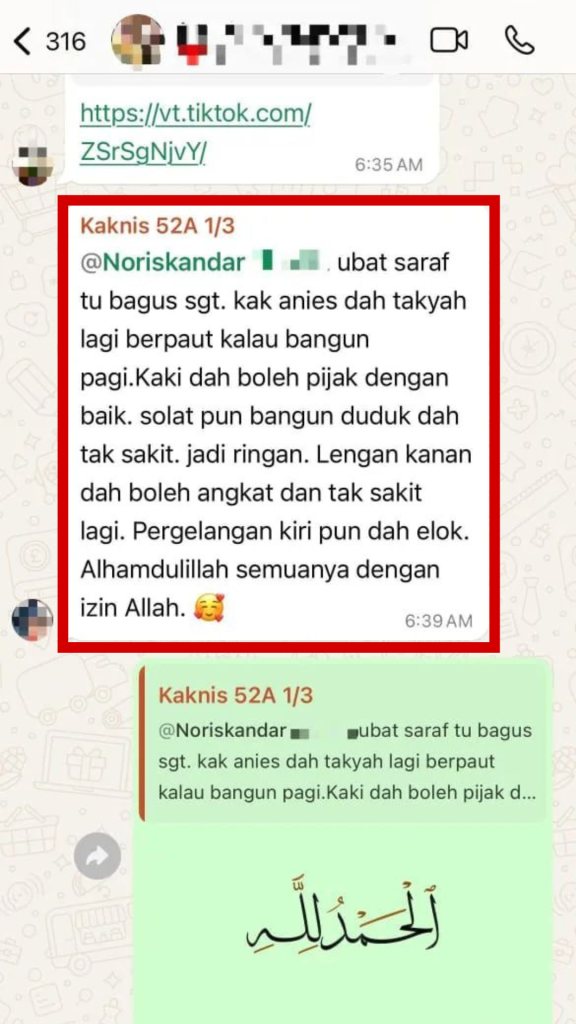

"6 Tahun Hadapi Masalah Saraf"

APA KATA MEREKA?

Naturmeric Terbukti Melegakan Secara Semulajadi Tanpa Kesan Sampingan!

"Dah 6 Bulan Tanggung DERITA MASALAH SARAF. Alhamdulillah lepas 3 jam, SAKIT HILANG!"